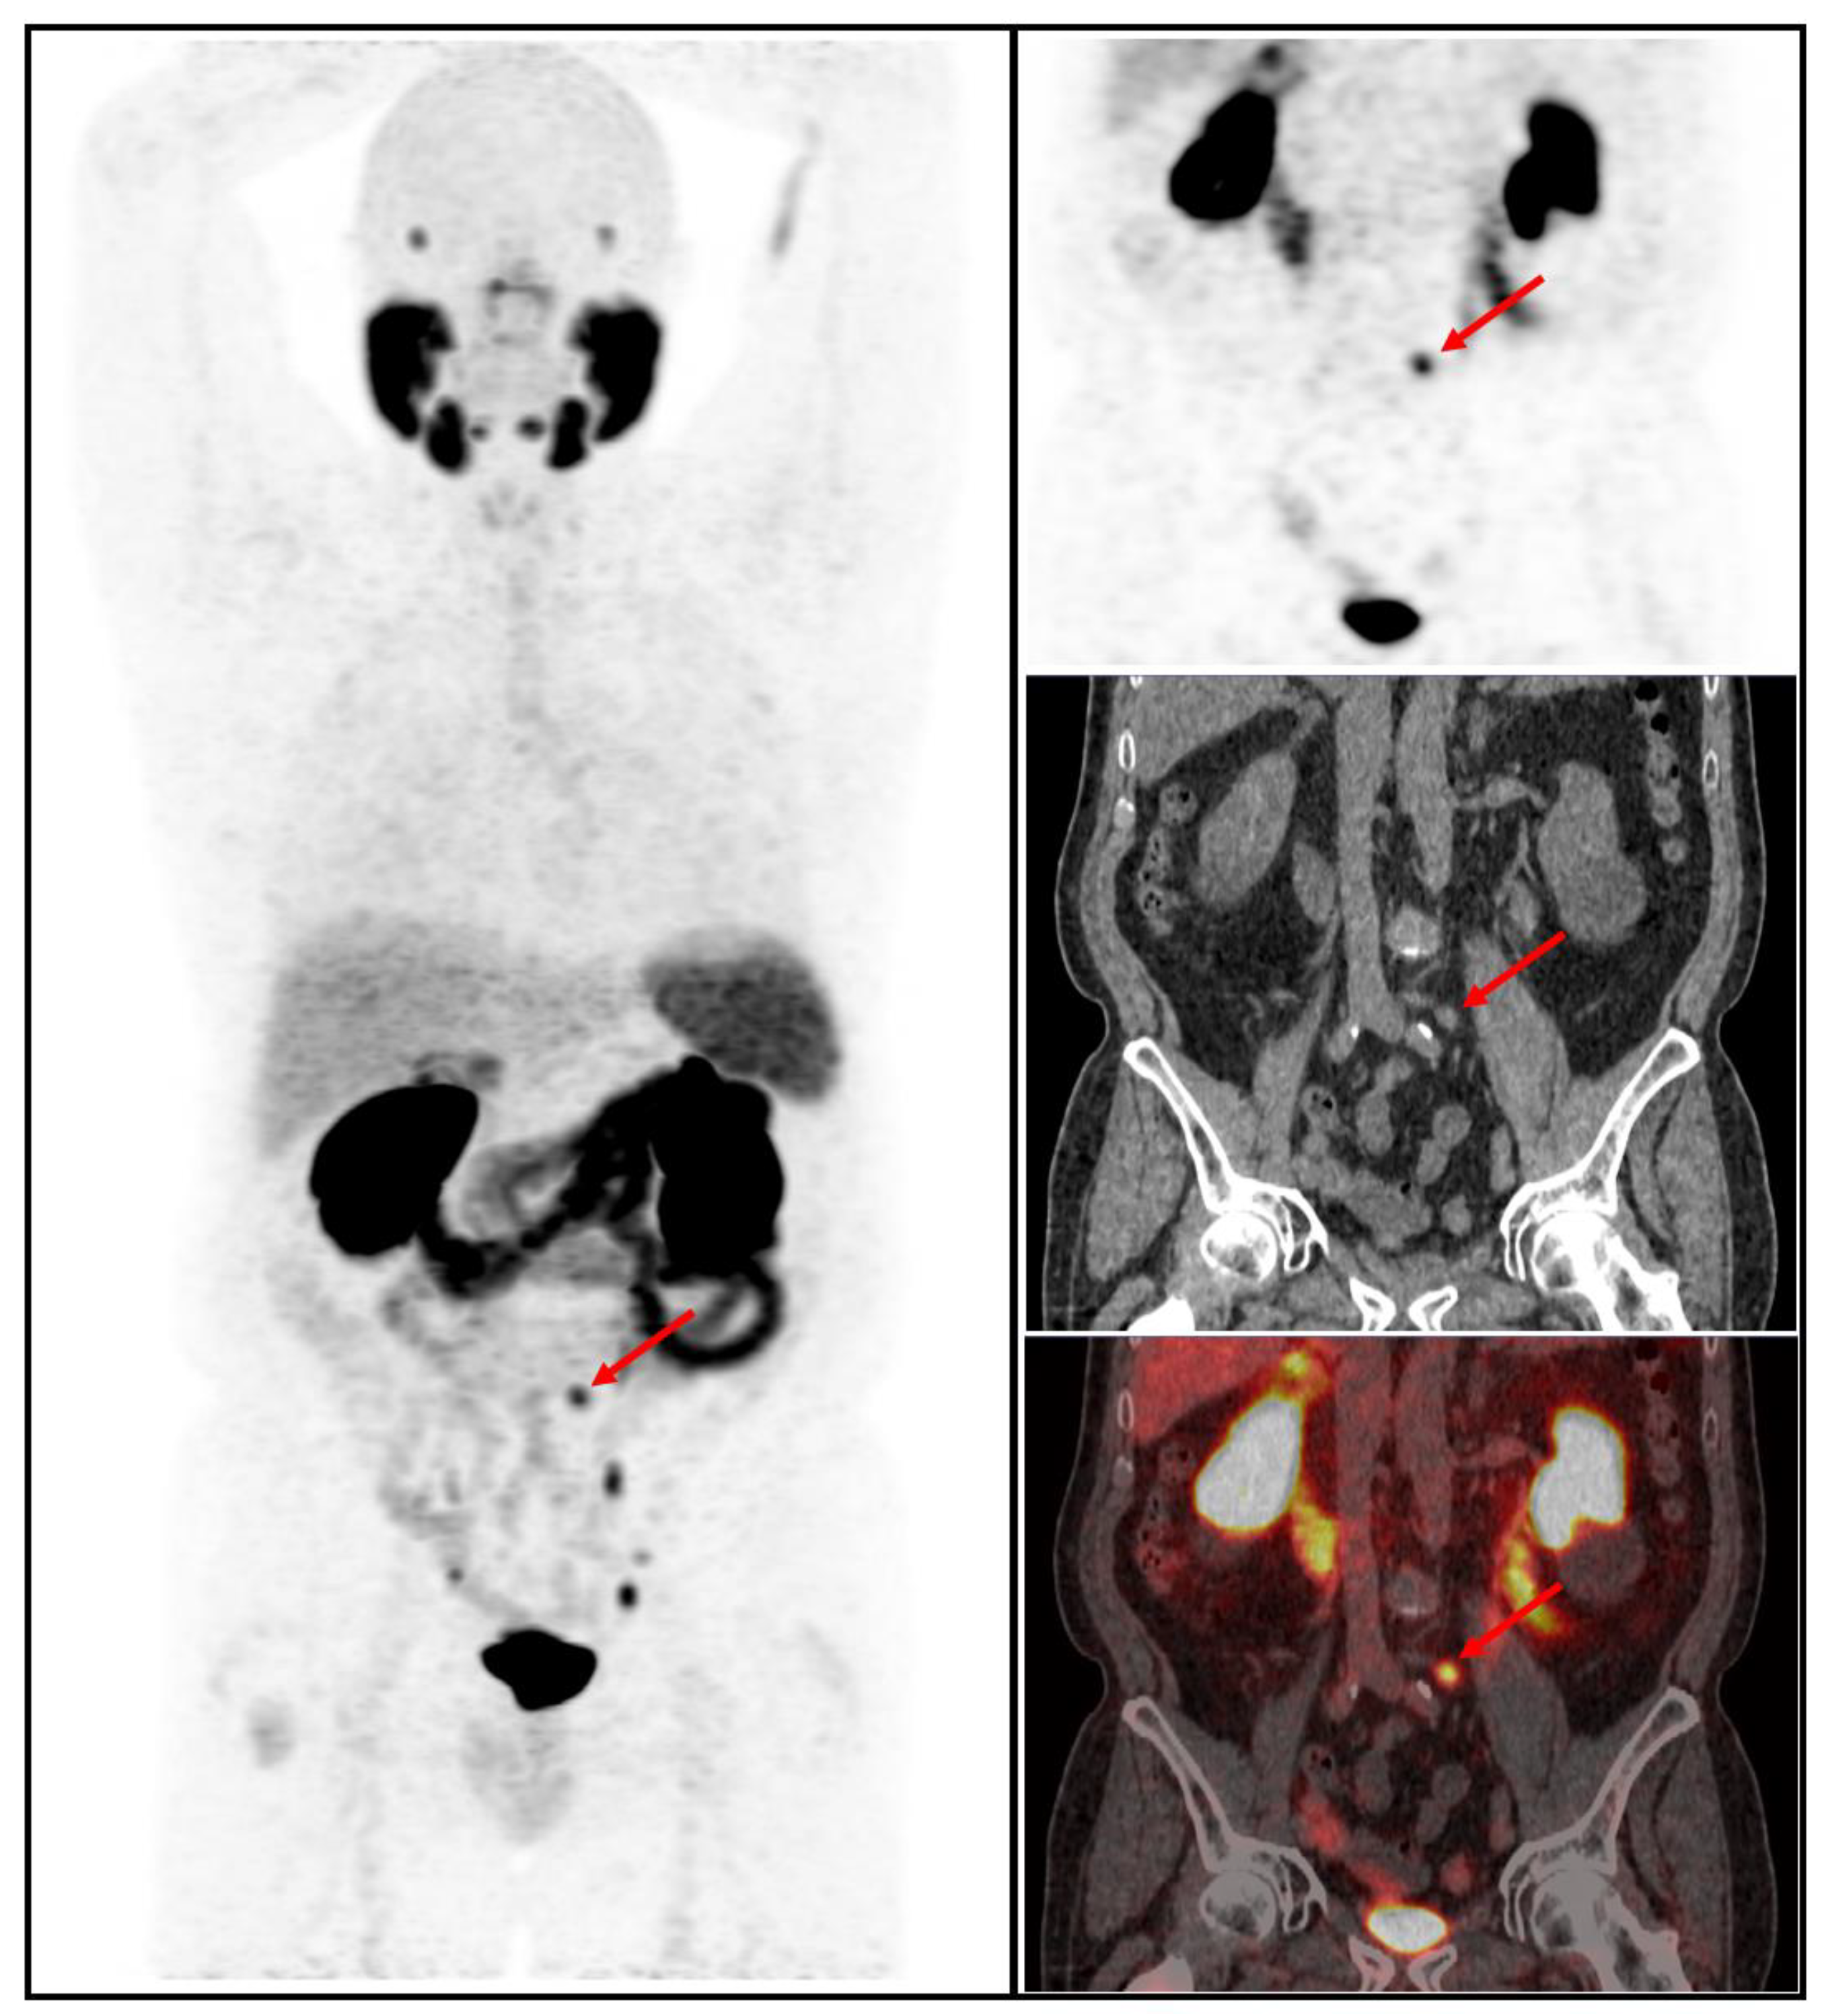

3.2. Imaging Findings